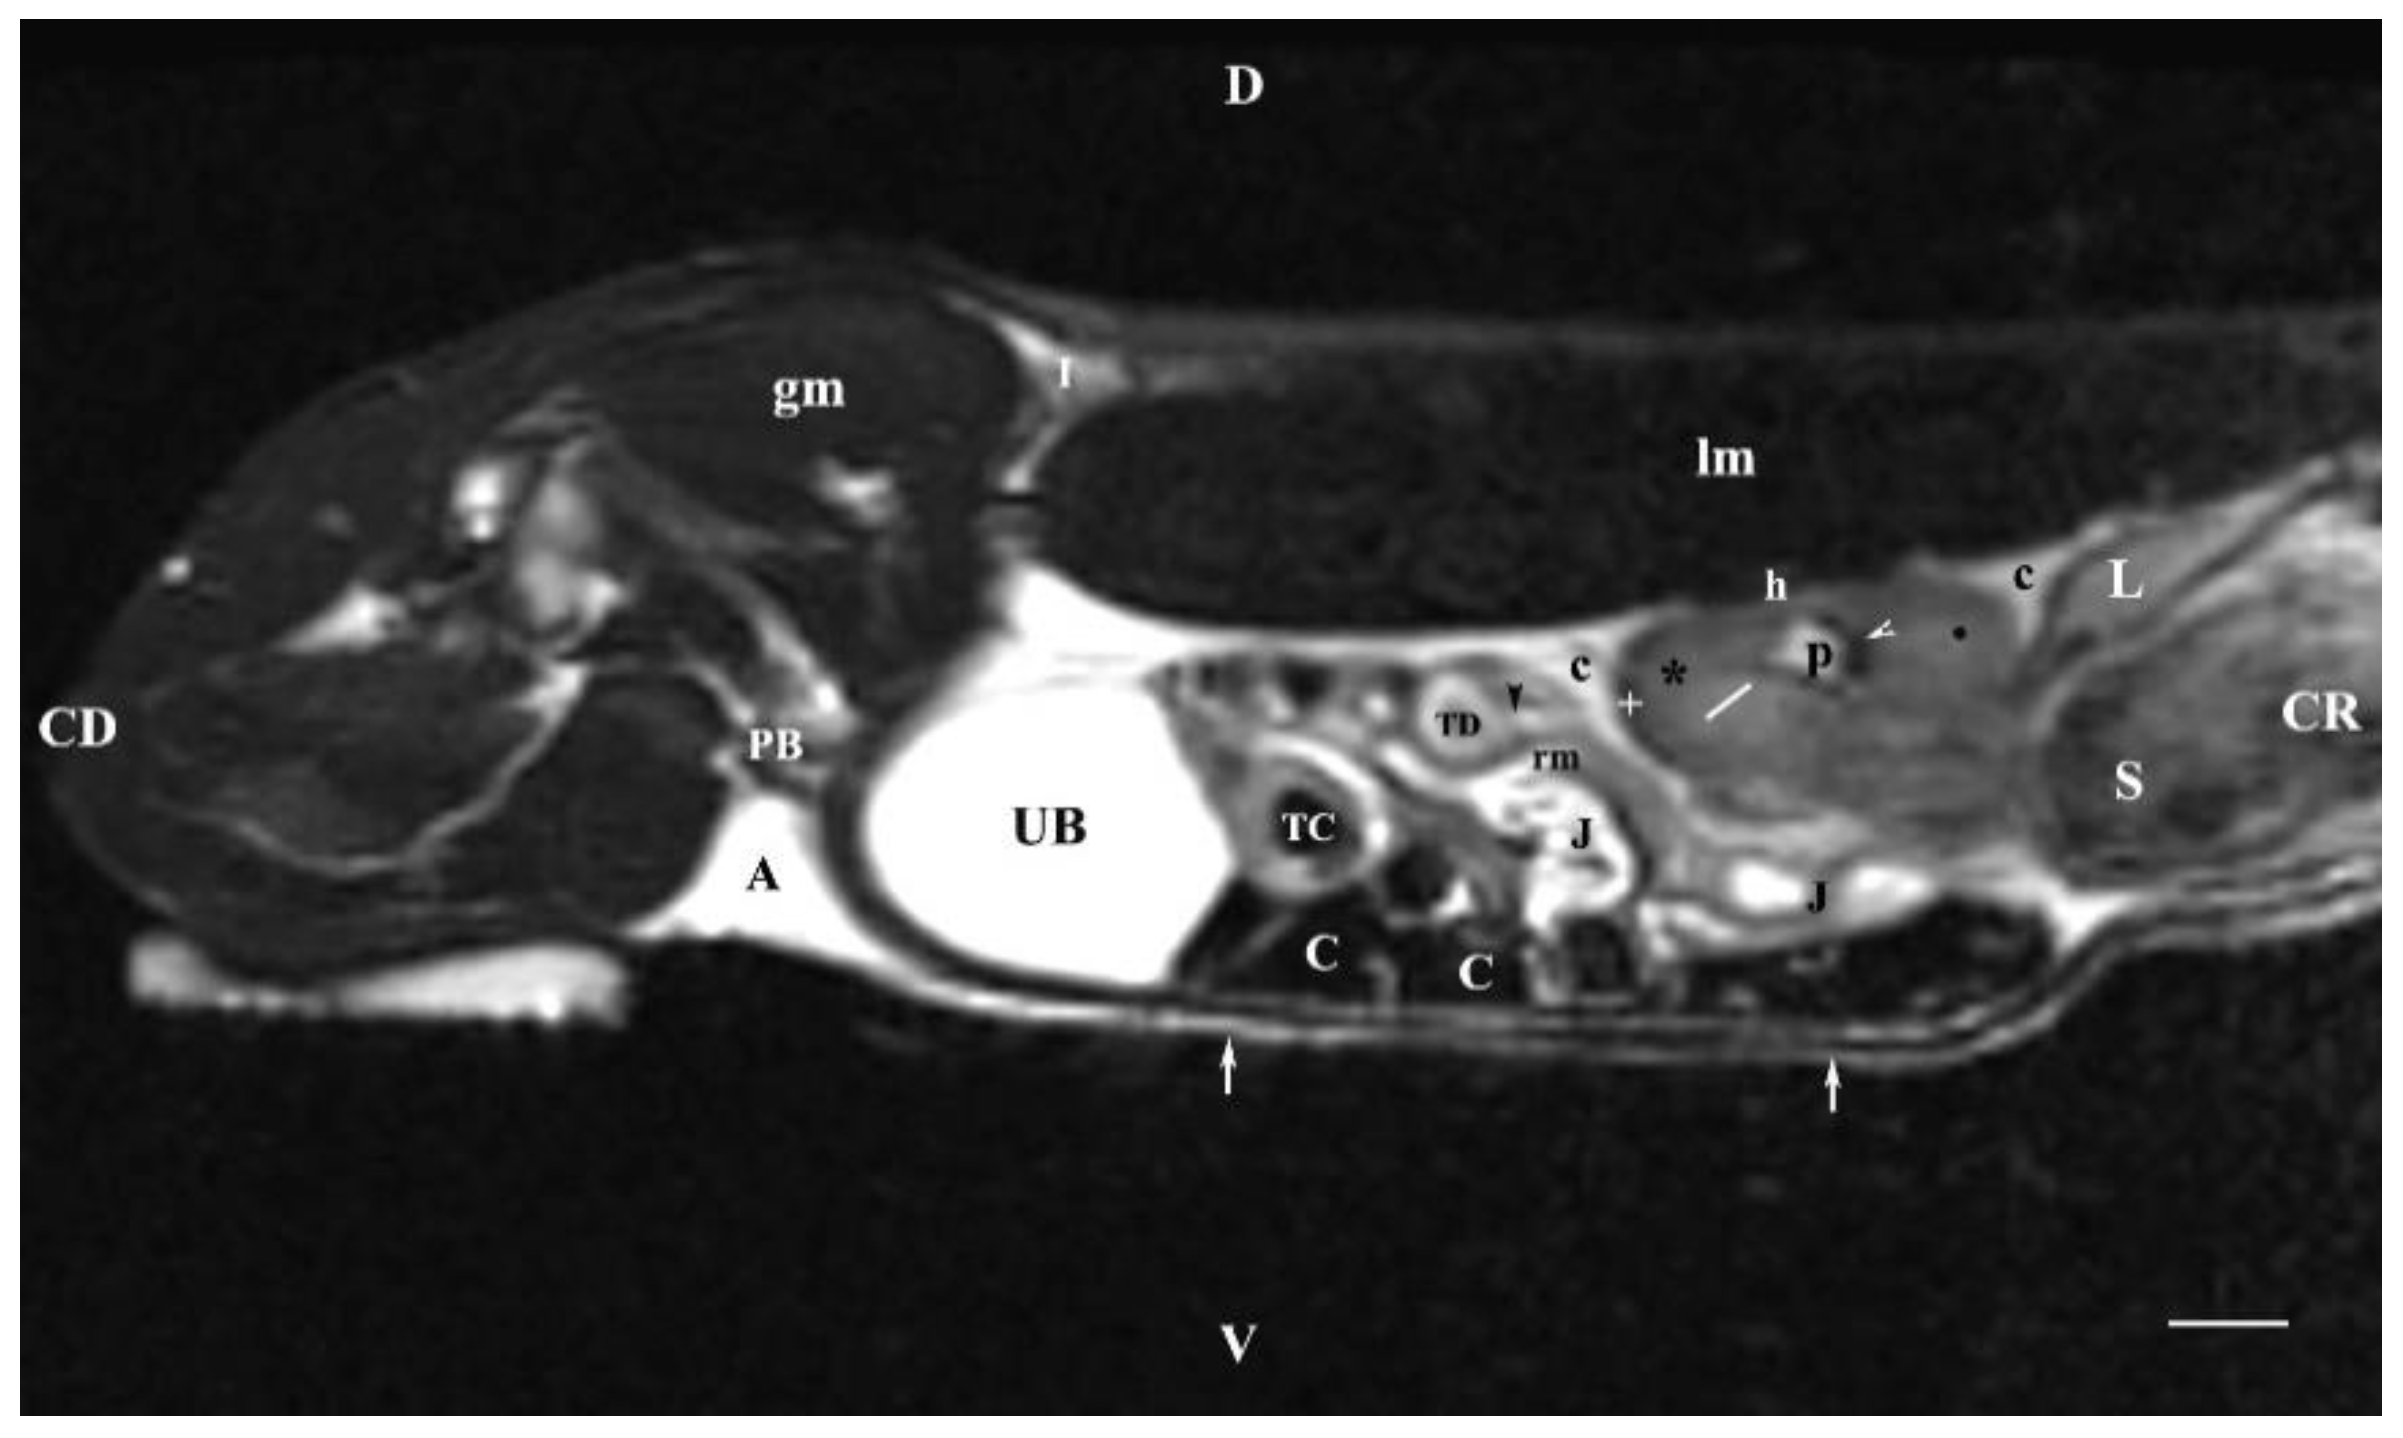

The sagittal T2-weighted image obtained 30 mm to the left of the median plane demonstrated the incomplete image of the left kidney (its lateral part) located in the lumbar area, the left ureter and the urinary bladder. The adipose capsule of the left kidney was clearly defined and hyper intense. The fibrous capsule was linear, hypo intense, with irregular outer and inner borders. The renal pelvis signal was hyper intense with indistinct peripheral outlines. The transition between the inner and outer medulla was not observed. The corticomedullary definition was marked. Similarly to the findings for the right kidney, the cortex and the medulla of the left one had various signal characteristics. Cranioventrally, the left kidney communicated with the spleen and the stomach, whose signal was heterogeneous and hyper intense. The left ureter was visualized as hyper intense tubular finding in the segment between the transverse colon and the urinary bladder. The bladder lumen appeared relatively hypo intense than its hyper intense wall. It was located in the caudal abdomen, and was with irregular shape and indistinct borders. The urinary bladder neck was not found on this section (Figure 8).

Figure 8. MRI imaging anatomy of organs from the middle abdominal region (sagittal section) (T2-weighted sequence 30 mm to the left of the median plane) (Left kidney). CD-caudal, CC-cranial, D-dorsal, V-ventral. (UB) urinary bladder; (p) renal pelvis; (white star) renal cortex; (white line) renal medulla; (white point) corticomedullary junction; (perpendicular white arrow down directed) renal hilus; (oblique white arrowhead) renal recessus; (white star) renal cortex; (perpendicular white arrowhead) ureter; (S) stomach; (SP) spleen; (c) renal adipose capsule; (white cross) fibrous capsule; (J) jejunum; (TC) transverse colon; (C) caecum; (PB) pubic bone; (I) ilium; (lm) longissimus muscle; (gm) gluteal muscle; (I) ilium; (white perpendicular arrow upward directed) abdominal wall. Line=10mm.

The sagittal T2-weighted MRI (30 mm left to the median plane) of organs demonstrated only the lateral part of the left kidney. The kidney possessed a heterogeneous intensity and partial definition of the different kidney parts due to the specific sequence option. Unlike the kidney finding, the abdominal part of the left ureter was visualized as a hyper intense tubular finding caudoventral to the left kidney. The hyper intense urinary bladder wall was due to the soft tissue character of the finding contrasting to its relatively hypo intense lumen.